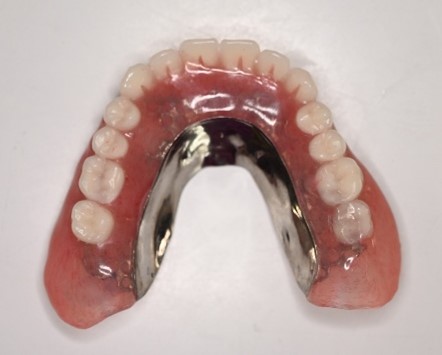

【マグネット式総入れ歯】

上顎

下顎